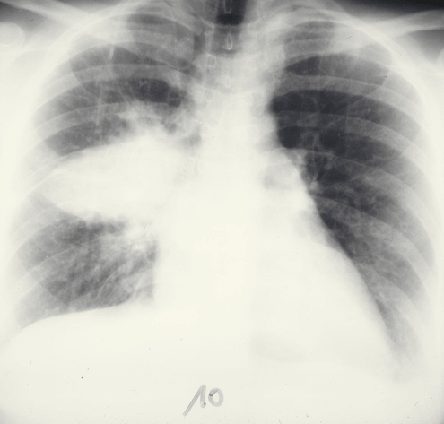

En particulier les pneumopathies

La tuberculose

Cette infection, en co-évolution avec le VIH, est l’une des plus graves parmi celles que l’on rencontre encore aujourd’hui, notamment chez les patients africains.